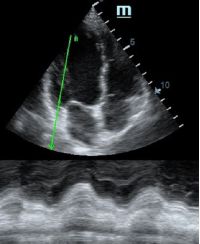

Но как же провести стандартные измерения в М-режиме, если мы его не использовали? На помощь приходит функция Free Xros M – анатомический М-режим. Имея записанную в память прибора видео петлю, мы можем провести линию М-режима в любом месте, при этом корректируя изначально не оптимальный угол.

TAPSE - показатель амплитуды движения латеральной части кольца трикуспидального клапана, позволяет количественно и быстро оценить систолическую функцию правого желудочка, норма которого составляет более 17 мм. Главным условием является проведение линии М-режима параллельно стенке правого желудочка в апикальном четырех камерном сечении, что легко достигается при Free Xros.